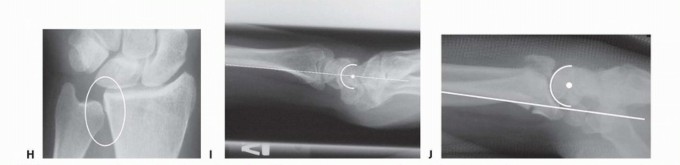

### FIG 4 • A. Positioning for standard lateral radiography. B. Standard lateral radiograph. C. Positioning for 10-degree lateral radiography. D. Ten-degree lateral radiograph. Note the improved visualization of the articular surface of the base of the scaphoid facet and the entire lunate facet. Injuries from a high-energy mechanism present as complex comminuted fractures of the articular surface with extension into the radial/ulnar shaft ( FIG 3I). ## IMAGING AND OTHER DIAGNOSTIC STUDIES Posteroanterior (PA), standard lateral ( FIG 4A,B), and 10-degree lateral views are routine views for radiographic evaluation of the distal radius. The 10-degree lateral view (FIG 4C,D) clearly visualizes the ulnar two-thirds of the articular surface from the base of the scaphoid facet through the entire lunate facet. Oblique views may also be helpful for evaluating the injury. The radiographic features of distal radius fractures include the following 8: Carpal facet horizon ( FIG 5A,B). This is the radiodense horizontal landmark that is used to identify the volar and dorsal rim on the PA view. If the articular surface has palmar tilt, the x-ray beam is tangential to the subchondral bone of the volar portion of the lunate facet, with the result that the carpal facet horizon identifies the volar rim. However, if the articular surface has displaced into dorsal tilt, the x-ray beam becomes tangential to the subchondral bone of the dorsal portion of the lunate facet instead, and the carpal facet horizon identifies the dorsal rim (not shown). The carpal facet horizon corresponds to the portion of the articular surface visualized on the 10-degree lateral x-ray projection. Teardrop angle (normal 70 ± 5 degrees; FIG 5C,D). The teardrop angle is used to identify dorsiflexion of the volar 79 rim of the lunate facet. Depression of the teardrop angle to a value less than 45 degrees indicates that the volar rim of the lunate facet has rotated dorsally and impacted into the metaphyseal cavity (axial instability pattern of the volar rim). This may be associated with axial and dorsal subluxation of the carpus. Restoration of the teardrop angle is necessary to correct this type of malreduction.

### FIG 5 • A. Carpal facet horizon (arrows). Used to differentiate between the volar and dorsal rim on the PA projection. B. Origin of carpal facet horizon. The carpal facet horizon is formed by that part of the articular surface that is parallel to the x-ray beam and depends on whether the articular surface is in volar or dorsal tilt. C. Normal teardrop angle. D. Depressed teardrop angle in this case is caused by axial instability of the volar rim. E. Normal articular congruency. F. Abnormal articular congruency, indicating disruption across the volar and dorsal surfaces of the lunate facet. G. AP interval is the point-to-point distance between the corners of the dorsal and volar rim. H. DRUJ interval. I. Normal lateral carpal alignment. J. Dorsal subluxation of the carpus. Congruency of the articular surface ( FIG 5E,F). The subchondral outline of the articular surface of the distal radius is normally both congruent and concentric with the subchondral outline of the base of the lunate; a uniform joint interval should be present between the radius and lunate along the entire articular surface. When the joint interval between these articular surfaces is not uniform, discontinuity and disruption of the lunate facet has occurred. Anteroposterior (AP) distance (normal: females 18 ± 1 mm, males 20 ± 1 mm; FIG 5G). The AP distance is the point-to-point distance from the dorsal to palmar rim of the lunate facet. It is best evaluated on the 10- degree lateral view. Widening of the AP distance implies discontinuity of the volar and dorsal portion of the lunate facet. 80 DRUJ interval ( FIG 5H). The DRUJ interval measures the degree of apposition between the head of the ulna and the sigmoid notch (normal: 2 mm or less). This parameter is best measured with the forearm in neutral rotation. Significant widening of the DRUJ interval implies disruption of the DRUJ capsule and TFCC. Coronal malalignment of the distal radial fragment is often suggested by widening of the DRUJ interval. Lateral carpal alignment ( FIG 5I,J). On the 10-degree lateral view and with the wrist in neutral position, the rotational center of the capitate normally aligns with a line extended from the volar surface of the radial shaft. Dorsal rotation of the volar rim results in a dorsal shift of lateral carpal alignment as the carpus subluxes dorsally. This may place the flexor tendons at a mechanical disadvantage, affecting grip strength. In addition to injury films, reassessing radiographs after reduction can be very helpful in determining the personality and specific components of a particular fracture. Computed tomography (CT) scans allow higher resolution and definition of fracture characteristics, particularly for highly comminuted fractures. Preferably, an attempt at closed reduction before obtaining a CT scan will help limit distortion of the image. CT scans are particularly helpful for visualizing intra-articular fragments as well as DRUJ disruption and incongruity of the sigmoid notch. Clinical evaluation of the carpus, interosseous membrane, and elbow, combined with radiographic studies when needed, should be included to identify the presence of other injuries that may affect the decision for a particular treatment. ## SURGICAL MANAGEMENT